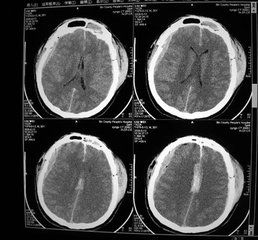

血腫圖示2.切割與穿戳切割是由於鋒利的物體作用於頭皮所致,往往造成邊緣整齊的頭皮裂傷。穿戳是由於尖銳的外物作用於頭部所致,往往造成規則或不規則的頭皮裂傷,且常伴開放性顱腦外傷。